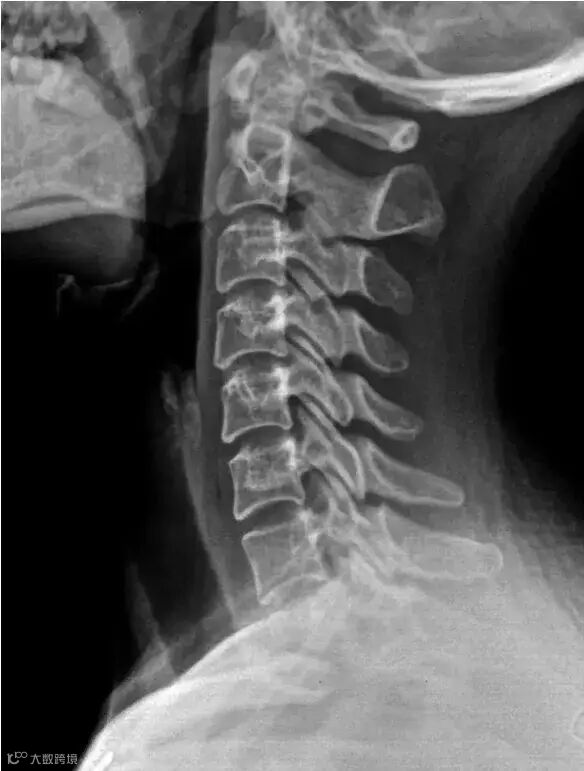

一.什么是颈椎病?

图中红色的部分就是人体的颈椎,它是由7块椎骨从上而下排列组成的。在这7块椎骨之间,有从上往下走的脊髓,脊髓就像我们的黄河一样,从颈椎一直流淌经过胸椎,再到腰椎,再到骶椎。其中颈椎处于这条河的上游,如果颈部的脊髓出状况,下游的全部脊髓神经都可能受影响。所以颈部脊髓的严重损害常导致截瘫,所谓截瘫,就是从某一个水平面以下的所有肢体感觉和运动功能均丧失。相当于上游被截流,下游就没水了。脊髓如下图黄色部分。